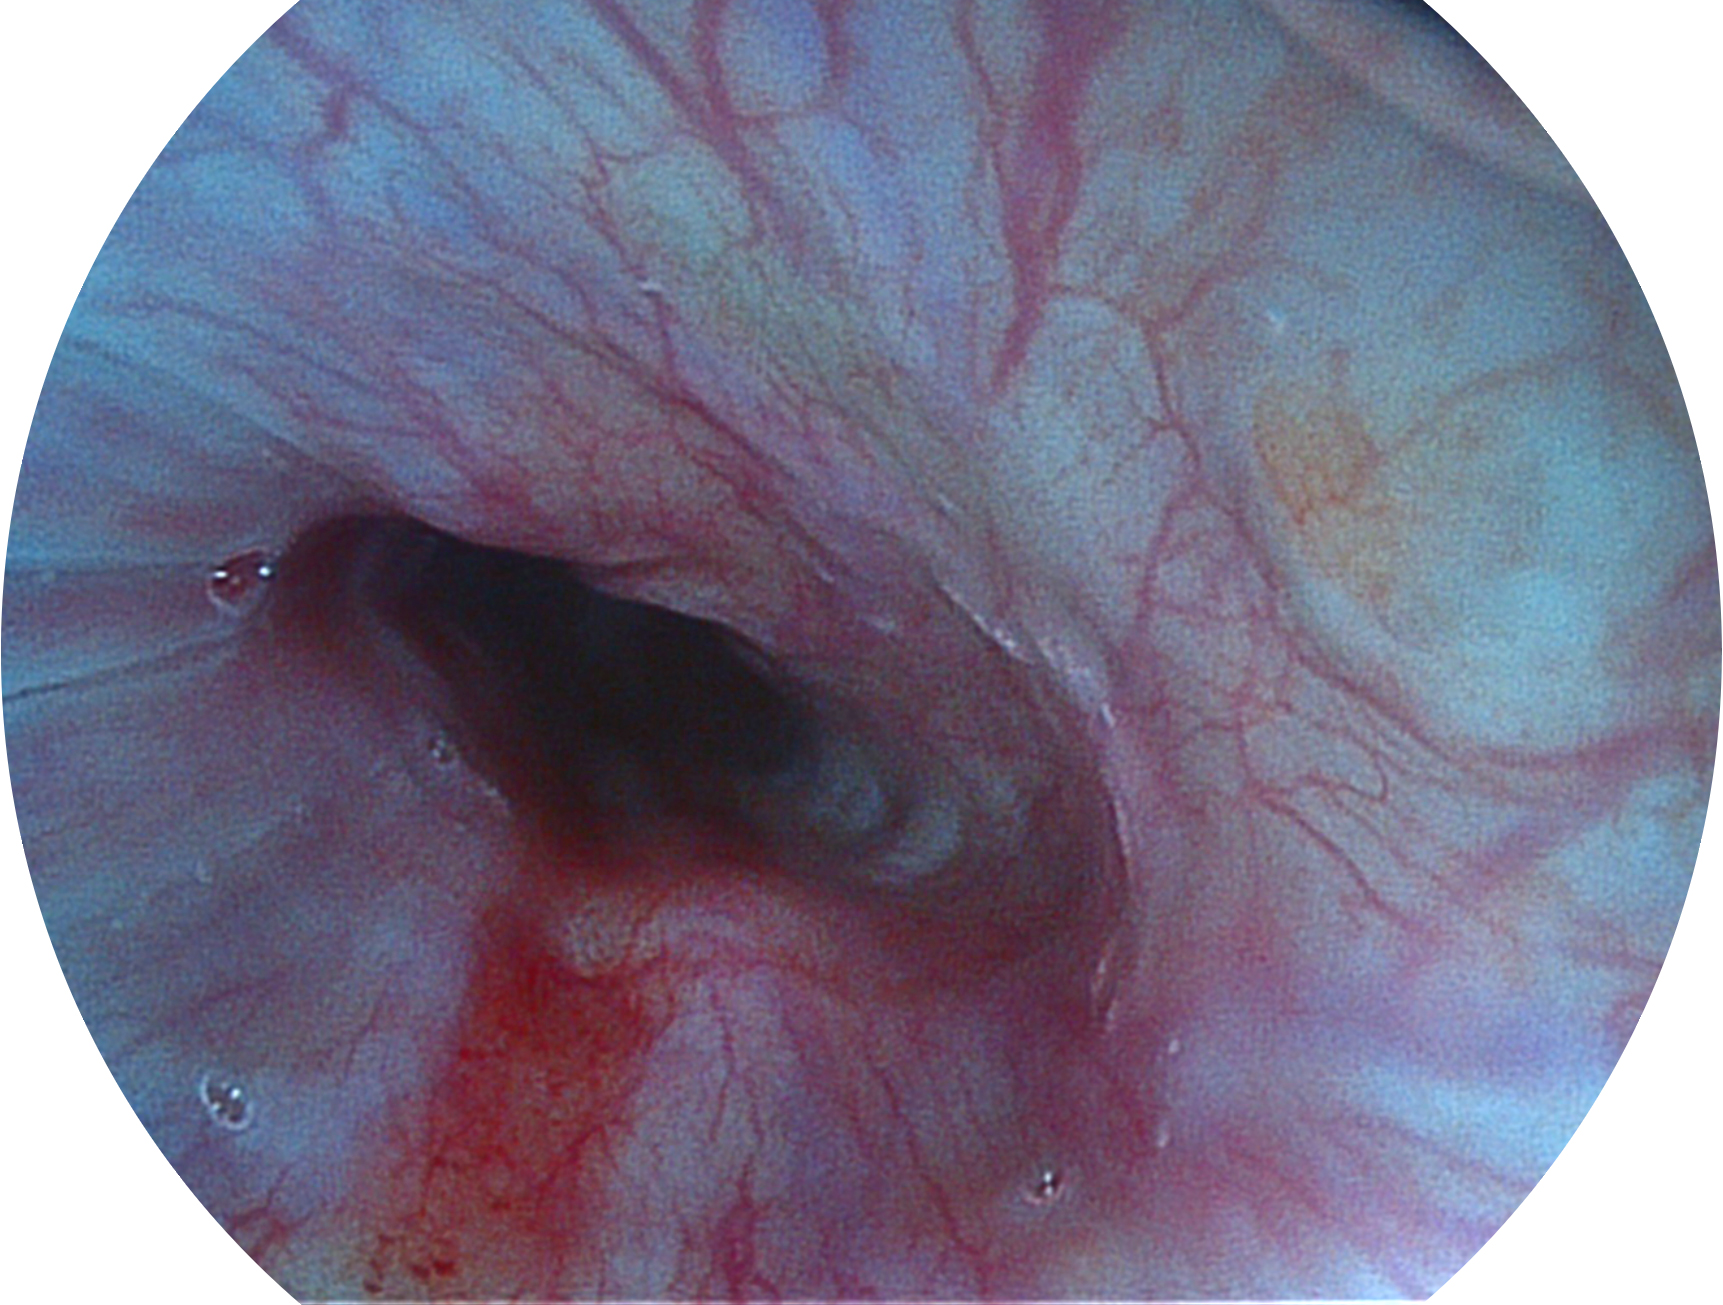

银河优越会新开发的内镜染色技术,主要是基于多波长LED 光源的开发,VLS-55Q 四波长LED 光源是由四个不同颜色的LED光按照相应照明模式所规定的特定发光比例进行合束后形成,合束后形成的照明光的光谱由红光、绿光、蓝光及蓝紫光这四个不同的波段范围构成。具有更高光谱自由度,通过光谱比例的控制,实现了聚谱成像技术,英文全称为“Spectral Focused Imaging, SFI”,缩写为“SFI”和光电复合染色成像技术,英文全称为“Versatile Intelligent Staining Technology, VIST”,缩写为“VIST”。